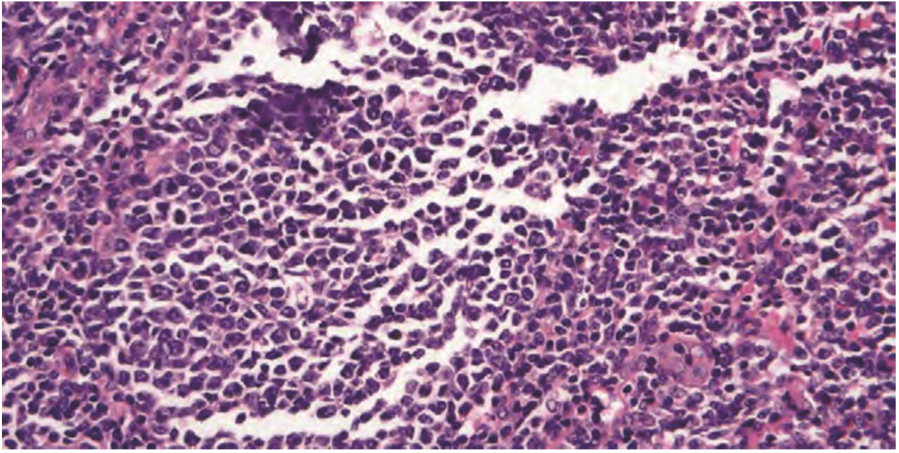

Obr: Tato lymfatická uzlina byla poškozena přehřátím kazetky ve vyhřívaném modulu zalévací linky. Všimněte si scvrknutých, pyknotických jader a rozsáhlých trhlin. Podobné praskliny mohou být také způsobeny napínáním řezů v příliš teplé vodní lázni nebo sušením řezů plovoucích na skle na velké kapce na horké plotýnce.